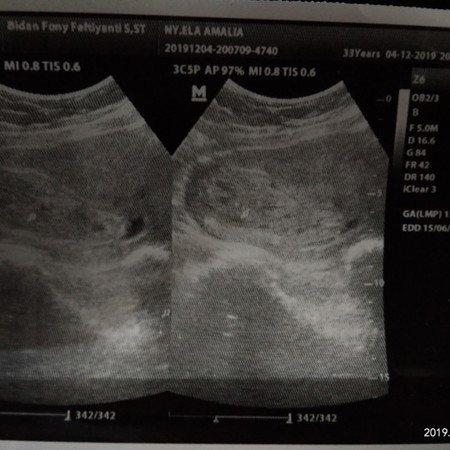

Hamil 12 minggu tapi kenapa janin tak terlihat?

Kata siapa nund itu s tengah tengah bkn janin kah